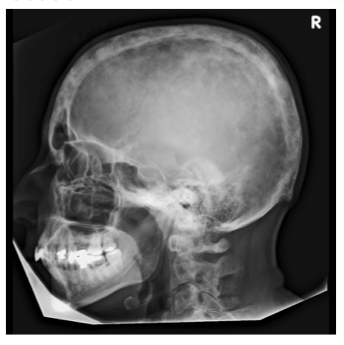

What clinical tests are there to assess bone structure?

What investigations would be done in suspected Paget’s disease?

What results would you expect?